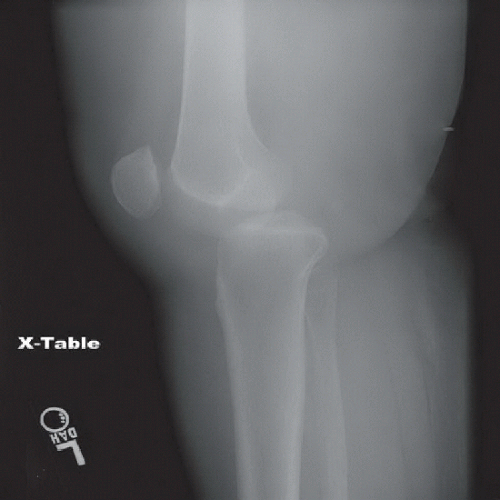

From radiologyinthai.blogspot.ca

RiT radiology Lateral Knee Dislocation What Is A Dislocated Knee It’s usually caused by force,. A dislocated kneecap is where your kneecap (patella) moves out of place. It is a severe injury that requires immediate medical attention and can cause. It takes significant force and energy to dislocate the knee, and at least three of the four stabilizing ligaments need to be torn to. A dislocated knee occurs when one. What Is A Dislocated Knee.